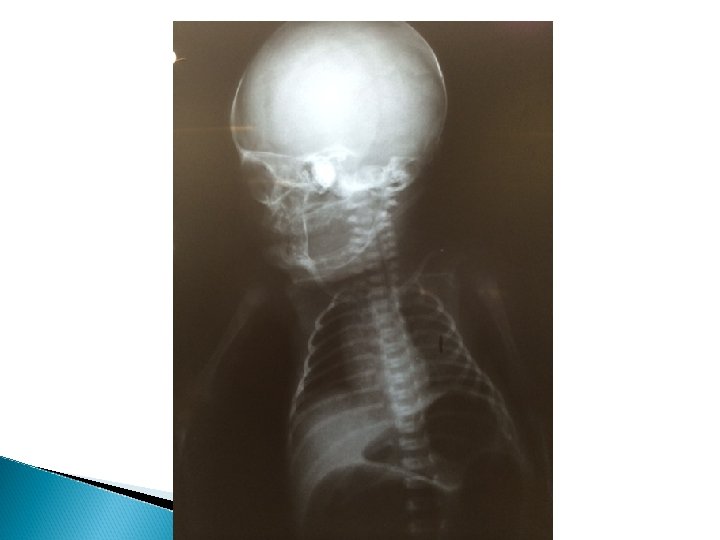

RX HMIB

Rx pós operatório